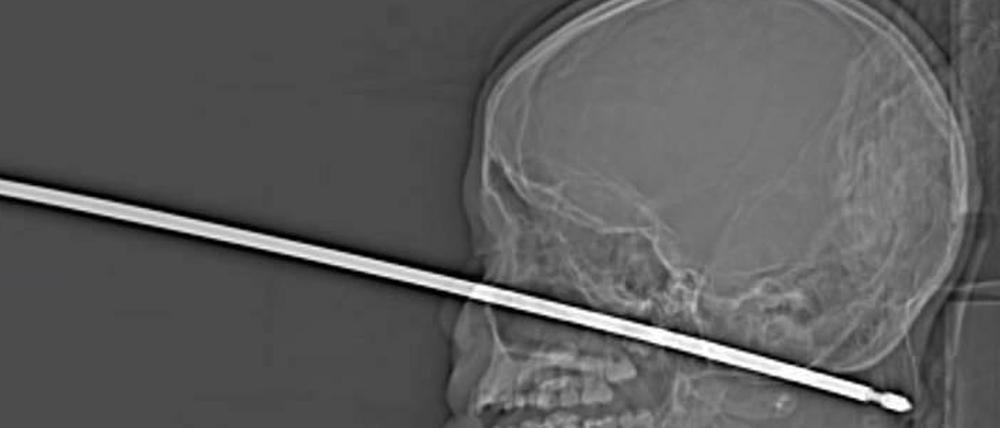

Ein 10-Jähriger flieht vor einem Insektenangriff und stürzt. Dabei rammt er sich einen Metallspieß ins Gesicht.

Dass der zehnjährige Xavier noch am Leben ist, grenzt nach Ansicht seiner Ärzte an ein Wunder: Ein Fleischspieß hatte sich in den Kopf des Jungen aus dem US-Staat Missouri gebohrt, wie der „Kansas City Star“ berichtete. Ereignet hatte sich das Unglück bereits am Wochenende. Xavier spielte in seinem Baumhaus, als er von Insekten attackiert wurde. Dabei stürzte er ab und landete auf dem Fleischspieß aus Metall. Dieser bohrte sich durch sein Gesicht in den Kopf. Sie habe Schreie gehört, erzählte seine Mutter Gabrielle dem Blatt. „Er kam herein, und dieses Ding steckte da drin.“

In einer sehr riskanten Operation entfernten Ärzte am Sonntag in der Klinik der University of Kansas den Metallspieß aus seinem Kopf. Der Spieß hatte weder Auge oder Gehirn noch Wirbelsäule verletzt, sagte Koji Ebersole. Auch wichtige Blutgefäße seien verschont geblieben, als sich der Spieß bis zu 15 Zentimeter in den Kopf des Jungen gebohrt habe. „Die Wahrscheinlichkeit davon liegt bei eins zu einer Million, das nichts davon getroffen wurde.“

Xavier habe sich sehr tapfer verhalten, sage Ebersole. Es sei ein Wunder gewesen, dass alles so gut ausgegangen sei. Die Ärzte gehen davon aus, dass er kaum oder keine bleibenden Schäden davontragen werde. (dpa)